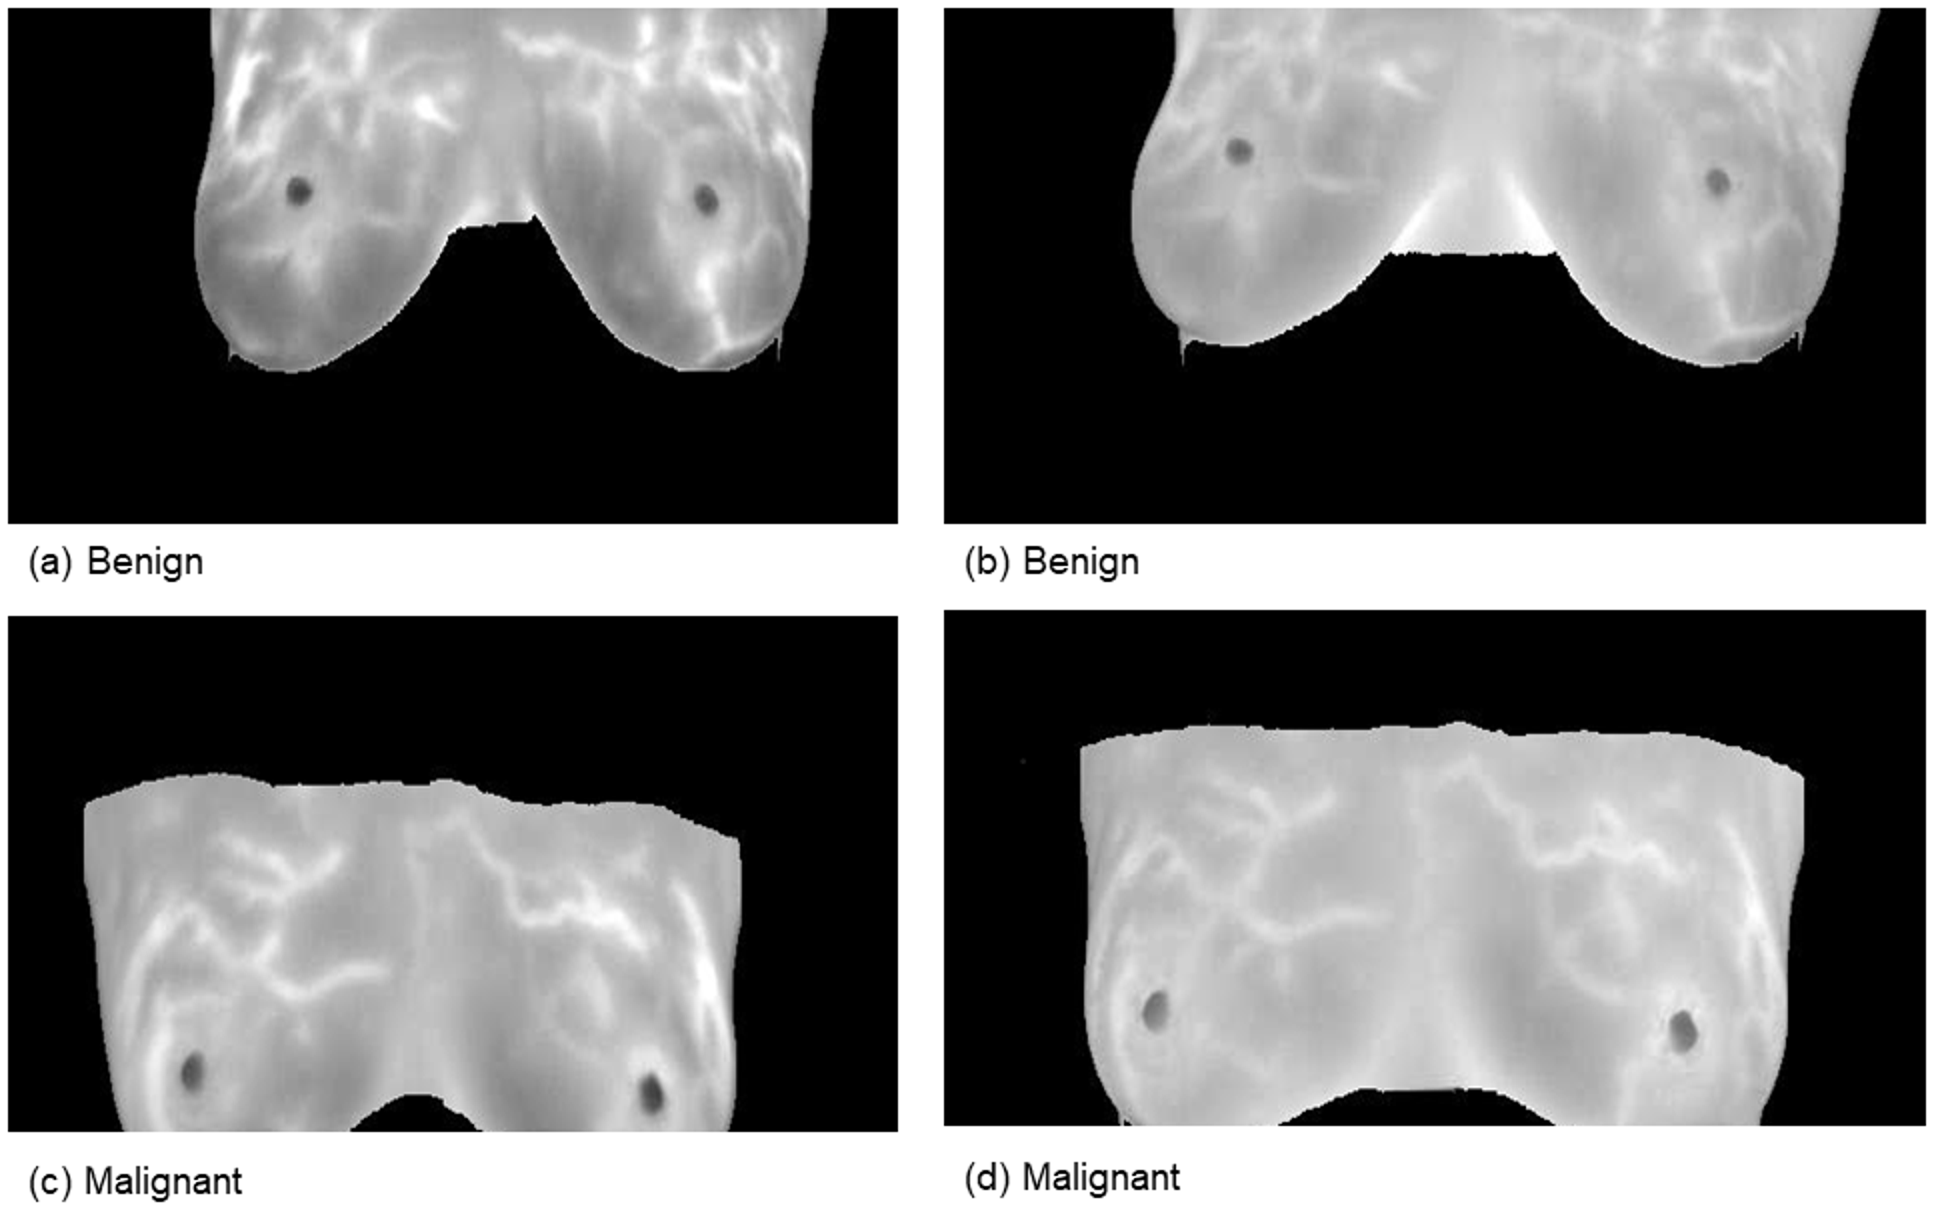

This comprehensive approach of utilizing datasets from multiple imaging modalities shown in Figure 1, Figure 2, Figure 3 and Figure 4 and summarized in Table 1, including mammography, ultrasound, MRI, and histopathological images, ensures robust model validation and enhances the system’s capacity to accurately classify benign and malignant findings. By leveraging these diverse datasets, we aim to develop a more generalizable and effective breast cancer classification system.

Figure 3. Samples from Ultrasound images.